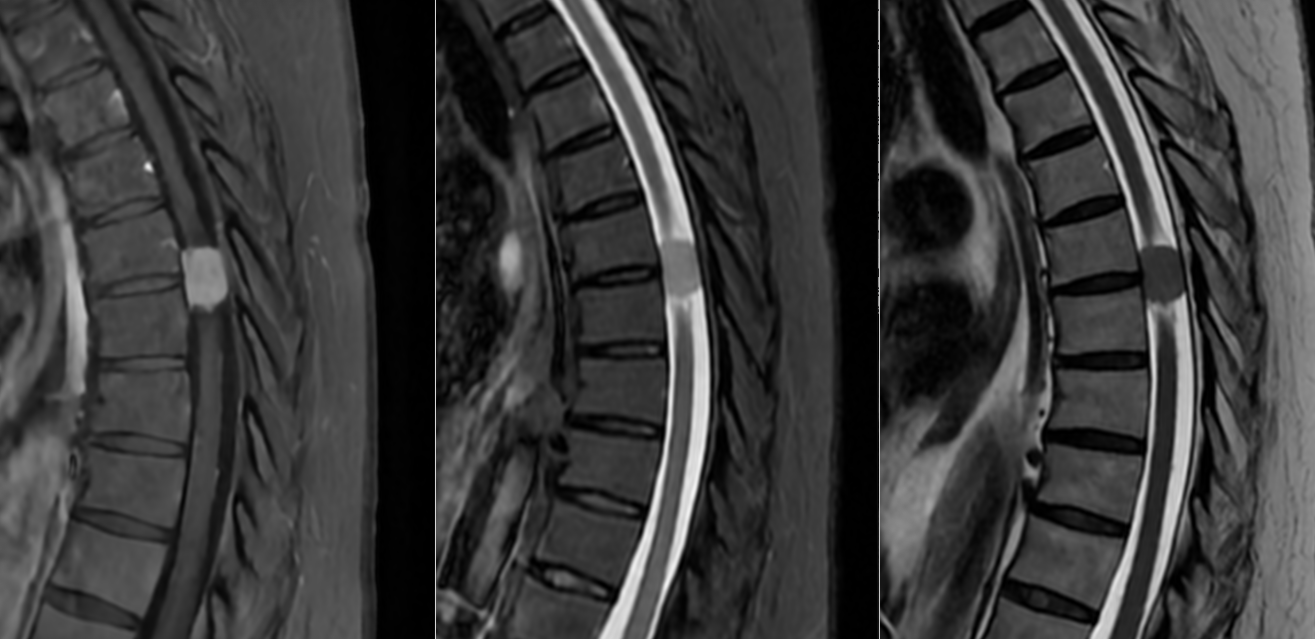

Meningiom spinal cervical C7-T1 – RMN preoperator

Meningiom spinal cervical C7-T1 – RMN postoperator